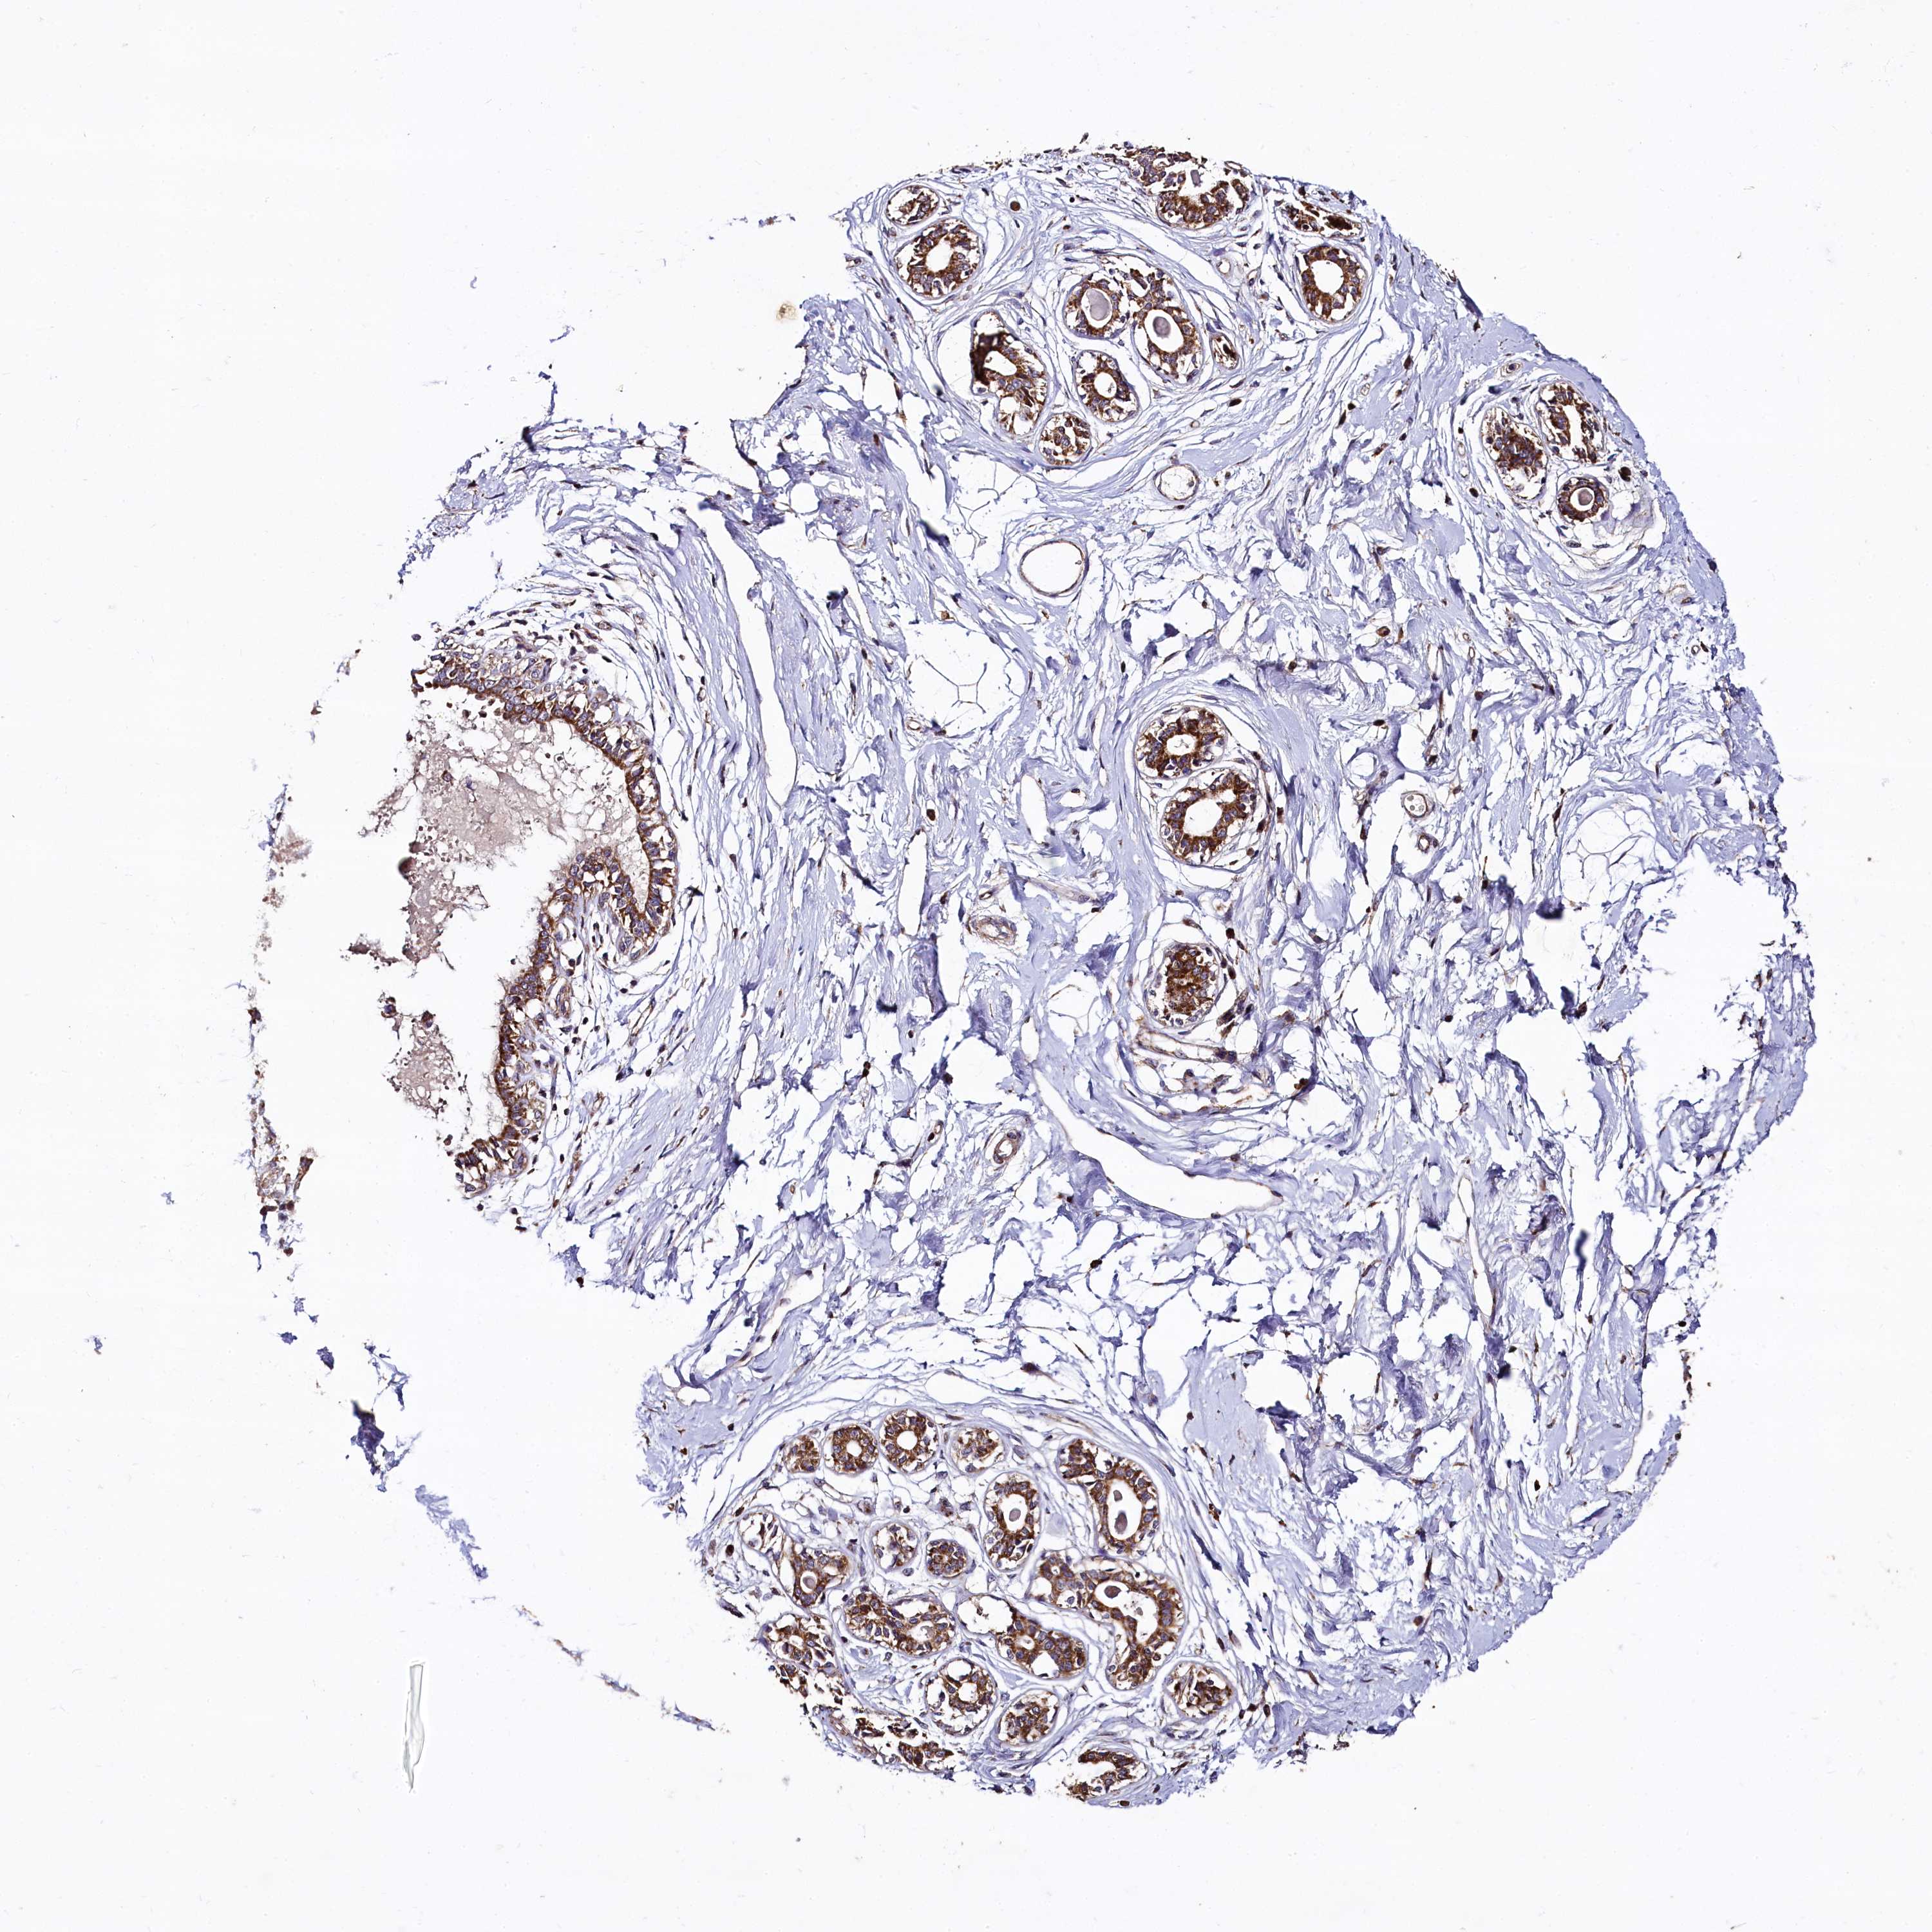

BREAST - Antibody stainingi

Antibody staining in the annotated cell types in the current human tissue is reported as not detected, low, medium, or high, based on conventional immunohistochemistry profiling in selected tissues. This score is based on the combination of the staining intensity and fraction of stained cells.

Each image is clickable and will lead to virtual microscopy that enables deeper exploration of all samples and also displays staining intensity scores, fraction scores and subcellular localization as well as patient and tissue information for each sample.

Antibody HPA040918

Adipocytes Not detected

Glandular cells High

Myoepithelial cells High